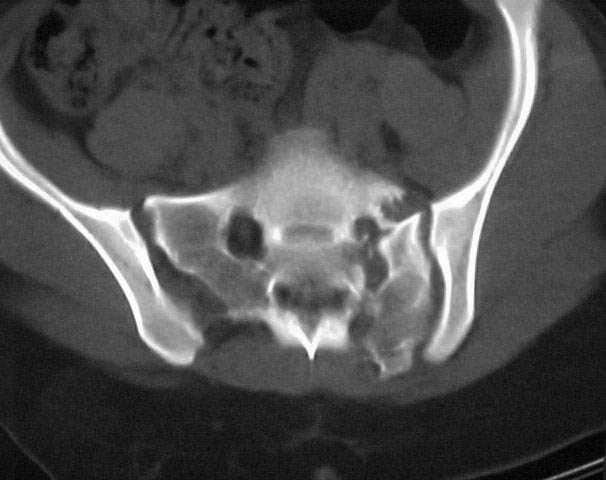

A 17 year old female involved in a car crash. Has a Type III lateral compression injury to her pelvic ring using the Young-Burgess classification. A windswept pelvis if you will. The images are included. There appears to be posterior displacement of the left hemipelvis as well.

Fx/Injury Evaluation:

Impression: unstable, requires reduction with stabilization, will continue with continued deformity if not stabilized

Thanks for submitting your case to the forum, I am sure you will soon be toxic with recommendations that you will have to filter through. I would like to offer some rather elementary advice: Your patient needs to have appropriate inlet and outlet films adjusted for her anatomy;i.e.,she appears to be somewhat lordotic and that would require the gantry angle to be adjusted with each view. The same would be true for the CT scan it appears as though the angle of the gantry is tangential to the slope of the sacrum (sacro-horizontal line if you will) and that gives a distorted view of the posterior ring injury.